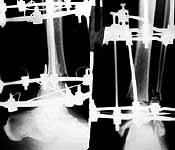

Thank you all for the kind responses. Kindly find attached the post op picture. I did an Ilizarov ring fixation which extended to the calcaneum. There was multiple small areas of partial thickness skin necrosis anteriorly and laterally which required split thickness skin graft.

Ilizarov device is a good choice, but I'm concerned about the valgus angulation (> 15degrees ?).

1. The reduction is in Valgus. Which you could correct on the Ilizarov and

2. The Lateral Malleolus is about 6mm superior to its normal position, which I don't know how you could correct.

Why connecting rods are bent?

As Dr Finlayson commented the fragments are malaligned. The combination of wires and pins in the middle ring makes correction at least inconvenient though of course it is always possible to re-assembly the frame and include hinges.

It would be quite enough to have either a 6 mm half pin or a olive wire inserted in frontal plane just above the fracture. The pin or wire would help to move the distal part of the shaft laterally (and a bit back) to align the fracture.

To give the follow up on this patient: A repeat X-ray showed the talus subluxating laterally. A dynamic inversion and eversion strain view pictures showed the lower tibio-fibular syndesmosis opening out. The frame was re-adjusted. Fracture site compressed and valgus corrected. A syndesmotic compression was achieved by adding a washer to the olive and pulling the comminuted lateral malleolus medially. another olive with washer given through talus lateromedially. The equinus that you may see has been corrected. Pictures attached. would welcome critical comments.